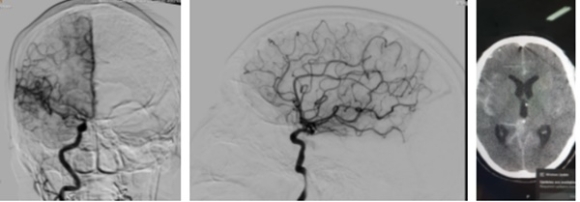

Hiện nay, Bệnh viện Đa khoa tỉnh Bắc Giang đang áp dụng phương pháp sử dụng thuốc tiêu sợi huyết để cấp cứu bệnh nhân đột quỵ não. Dùng thuốc tiêu sợi huyết sẽ có tác dụng làm tan cục máu đông, tái thông mạch máu não của người bệnh. Tuy nhiên thuốc tiêu sợi huyết chỉ có tác dụng tối ưu đối với bệnh nhân đột quỵ não tại một thời điểm nhất định và thời điểm "Vàng" để sử dụng thuốc tiêu sợi huyết cấp cứu đột quỵ não là từ 3 giờ đến 4,5 giờ tính từ thời điểm khởi phát các dấu hiệu như méo miệng, lưỡi tê cứng, yếu nửa người, không nói được, khó nói, mắt mờ, đau đầu... Vì vậy, để kết quả điều trị đạt hiệu quả tốt nhất, cần phát hiện sớm các dấu hiệu đột quỵ não và đưa người bệnh đến bệnh viện càng sớm càng tốt. Nếu quá thời gian vàng, người bệnh sẽ không được chỉ định dùng thuốc tiêu sợi huyết.